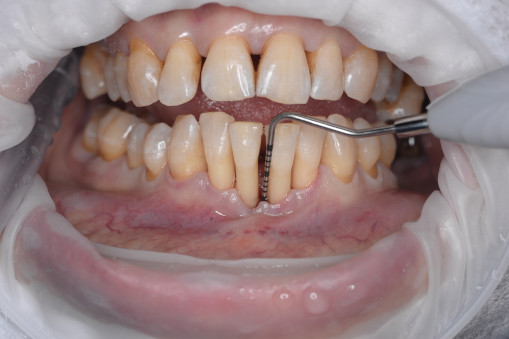

А прежде, чем вы посмотрите фотографии «до» и «после» лечения слизистой оболочки полости рта, проведенных в нашей клинике, хочу поблагодарить большое количество наших пациентов, которые поверили, прониклись нашей концепцией, и мы вместе, именно вместе победили болезни десны, гингивит и пародонтит!

До/после лечения